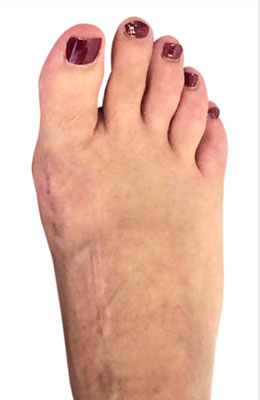

Before

Minimally Invasive Bunion Surgery featuring the CrossRoads miniBunion™ System before

After

Minimally Invasive Bunion Surgery featuring the CrossRoads miniBunion™ System after

Minimally Invasive Bunion Surgery featuring the CrossRoads miniBunion™ System

Eva is a 24-year-old female who had just began working at a job that required high fashion shoes. She was in constant pain but could not take time off work. Our miniBunion™ Minimally Invasive Bunionectomy allowed her to continue to work and be on her foot with full recovery and return to regular shoes by 6 weeks. She had an amazing range of motion, no more bunion pain, and absolutely no visible incision. After picture taken six weeks post-surgery.